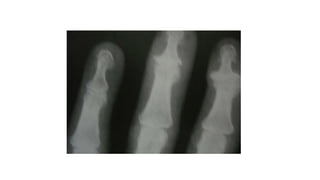

Caso clínico 3 •M.S.O.S. 66ª, Dor nas mãos há 1 ano e meio, que no início da doença era mais intensa ao acordar e diminuía ao longo do dia, porém com a progressão da doença a dor tem ocorrido o dia todo; • Rigidez nas articulações das mãos de menos de 1 hora • Inchaço nos dedos; • Dificuldade para realizar movimentos simples, como pegar um objeto ou escrever, por exemplo; • Formigamento das mãos, mesmo em repouso.

Caso Clínico 3 •Verificada a formação de nódulos nas articulações, como o nódulo de Heberden, que é formado na articulação Interfalangeana distal, e o nódulo de Bouchard, que é formado na articulação interfalangeana proximal. • Dor a palpação das Interfalangeanas distais e Interfalangeanas proximais.